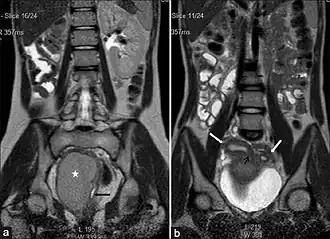

| (a) Imagem coronal de T2W de tomada única mostra ausência do rim direito. A hemivagina distendida (asterisco) é vista no lado direito e a hemivagina esquerda normal colapsada com fluido mínimo é vista adjacente a ela (seta preta). A hemivagina distendida termina acima do introito e seu conteúdo é hipointensa à gordura. (b) Imagem coronal de T2W de tomada única mostra os cornos uterinos direito e esquerdo (setas brancas). A cavidade do corno uterino direito é vista se comunicando com a extremidade superior da coleção de fluido na hemivagina direita (pequena seta preta). | |